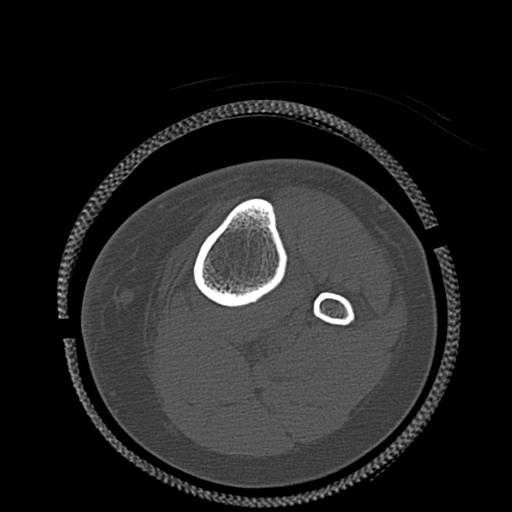

82084 1/14 1/20 股関節 2R 78歳男性 右人工骨頭